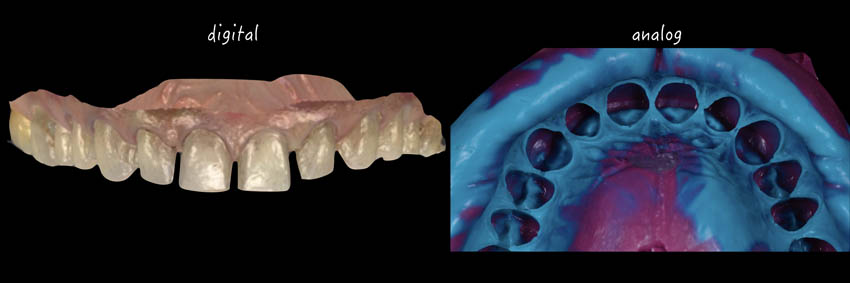

The synergy between digital and analog workflow. When and how?

Initial impression. Analog and digital workflow. CR registration using anterior deprogrammer.

Traditional vs Digital: when and why choose the digital path

Intraoral scanning: scanning protocol and precision